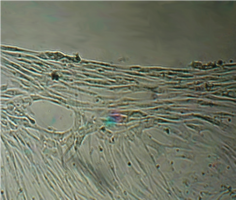

6 серия экспериментов. Образец исследуемого материала (аллогенный ГАП серии «Лиопласт»® массой 2 мг) помещали на дно культуральной чашки, после чего высевали фибробласты в стандартной концентрации.

Щелочной материал резко ухудшает прикрепление фибробластов к дну культуральных чашек (рис. 35) на всей его площади, вместе с тем прикрепившиеся клетки имеют четкие границы, нуклеолемма четко контурирует, цитоплазма гомогенная, без патологической зерностости, вакуолей и включений.

Рис. 35. Выраженная пролиферация, восстановление плотности монослоя.

Фибробласты лишь более распластаны по дну чашки, но это характерно для культуры с малой плотностью.

Вокруг образца через сутки от начала эксперимента клетки не прикрепляются (расстояние от края образца до границы 1,3±0,12 мм).

В последующие дни и до конца наблюдения плотность монослоя  в отдаленной от образца зоне нарастает даже несколько быстрее, чем в контроле, клетки сохраняют обычную для фибробластов в культуре морфологию.

Большое количество слущенных клеток в ростовой среде объясняется ухудшением прикрепления пассированных клеток, а не гибелью уже прикрепившихся (табл. 14).